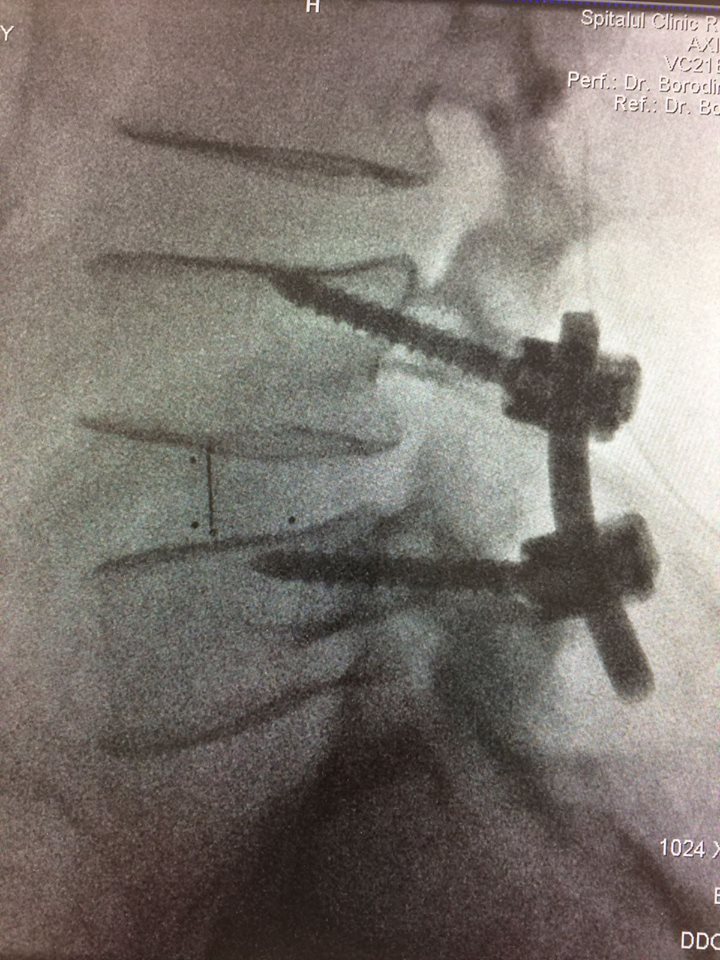

Echipa de specialiști în neurochirurgie spinală a Spitalului Clinic Republican a obținut o nouă realizare. S-a reușit o fuziune intervertebrală cu șuruburi transpediculare și cușcă intervertebrală printr-o incizie mai mică a pielii, de doar 4 cm, recordul anterior fiind de 5 cm. Succesul intervenției se datorează folosirii tehnologiilor moderne (CT intraoperatorie, Neuronavigația spinală, Neuromonitoring intraoperator) și planificării preoperatorii detaliate.

Pentru tratarea unui pacient de 63 ani cu diagnosticul de Spondilolistezis instabil L4-5, însoțit de stenoză de canal lombar, a fost folosit un abord chirurgical nou - Fuziunea Intervertebrală Mediană.

Procedura a început sa fie aplicată în clinică din ianuarie 2016. Până în prezent, folosind tehnica nouă, au fost operați peste 30 de pacienți.

Intervenția chirurgicală de acest gen presupune o incizie mai scurtă, mobilizare limitată a țesuturilor și, respectiv, o hemoragie redusă. Durerea postoperatorie este mai mică, iar reabilitarea are loc mai rapid.